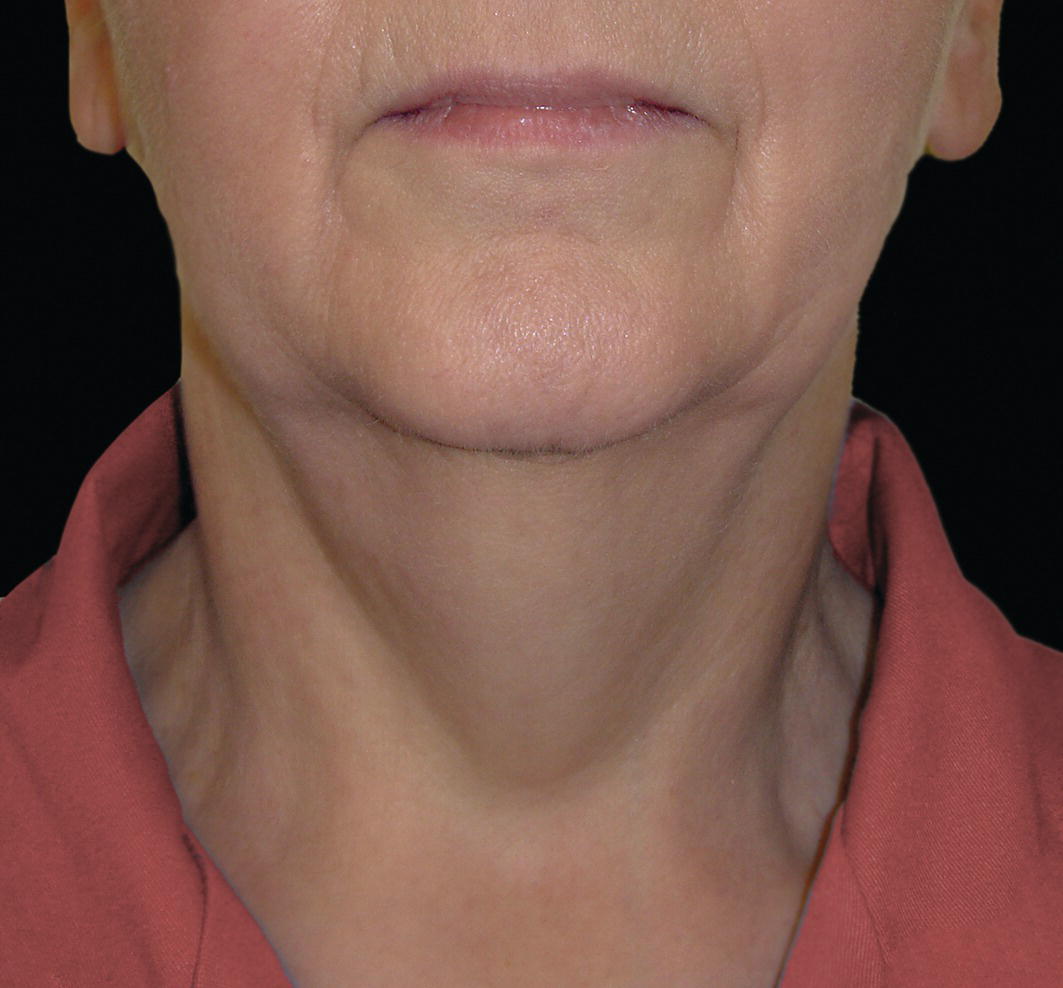

The morphology of the upper aspect of the neck and its transition with the submental region has a major impact on the aesthetics of the lower face. The anterior part of the neck extends no higher than the inferior border of the mandible. The hyoid bone is connected to the mandible by a thin sheet of muscle, the mylohyoids, which form the upper limit of the anterior part of the neck and separate the mouth from the neck. Superficially (i.e. below the mylohyoids) lies the anterior belly of digastric, while lying above it, half hidden under the mandible in the submandibular fossa, is the submandibular salivary gland (Figure 21.1). These structures are covered in by the investing layer of deep cervical fascia, which is attached to the hyoid bone and the inferior border of the mandible. The platysma muscle lies in the subcutaneous tissues. It forms a broad, flat sheet, extending from the deep fascia over the upper part of pectoralis major and the most anterior part of deltoid to the inferior border of the mandible, with some fibres reaching the lateral part of the lower lip. The sternocleidomastoid muscle forms a prominent neck landmark and may be made to stand out by turning the head towards the opposite side against resistance. The two heads of origin are from the sternum and medial one‐third of the clavicle; its attachment is to the mastoid process, which forms a readily visible and palpable bony landmark behind the lobe of the ear (Figure 21.2). Figure 21.1 Submental anatomy in relation to the mandible, with muscle attachments: Despite its importance in facial aesthetics, there is much confusion in terminology relating to the description and analysis of the submental‐cervical region. For example, the cervicomental angle has been described by perhaps half a dozen different methods, depending on the describing authority. Appropriate terminology is essential for the evaluation and accurate description of submental‐cervical aesthetics (Figure 21.3). Figure 21.2 Profile view of the face and neck with superimposed bony and muscular outlines: Cervical point (C‐point or ‘point C’): The innermost (posterior‐superior) point between the submental plane and the anterior aspect of the neck in the midsagittal plane, located at the intersection of lines drawn tangent to the submental region and the anterior neck. Submental plane: A plane or line constructed between the cervical point (C‐point) and the most inferior point on the chin (soft tissue menton, Me’). If C‐point cannot be defined, the submental plane is drawn tangent to the submental contour passing through soft tissue menton. The submental plane is referred to as the ‘throat’ plane by some authorities; the submental length (distance from C‐point to menton) is therefore sometimes referred to as the ‘throat length’. Cervical plane: A plane or line drawn tangent to the anterior soft tissue contour of the neck above and below the thyroid prominence. Figure 21.3 Submental plane, cervical plane and cervical point (C‐point). A thorough understanding of the aetiological factors involved in creating a poor aesthetic contour of the submental‐cervical region is required in order to diagnose and appropriately plan the correction of the aesthetic submental‐cervical angles and contour. The tonicity of the submental‐cervical skin, the muscular support of the neck, the isolated fatty deposits in the submental‐cervical region, the skeletal framework of the mandible and chin, and the spatial position of the hyoid bone are all important parameters in the aesthetic analysis of the submental‐cervical region. An undesirable submental‐cervical contour may result from: It is paramount that the clinical evaluation is undertaken with the patient in natural head position (NHP). Even a small degree of upward or downward tilting of the head must be avoided as it may have a profound effect on the contour of the submental‐cervical region. A number of parameters may be analysed in the clinical evaluation of the submental‐cervical region: Mandibular and/or chin deficiency in the sagittal plane, and/or posterior (downward and backward) rotation of the mandible, often secondary to vertical maxillary excess, may contribute to the undesirable aesthetic appearance of the submental‐cervical region (Figure 21.4). It is helpful to have the ‘Class II skeletal pattern’ patient posture the mandible forward to a more normal sagittal position, which will concurrently stretch the submental soft tissues. If this manoeuvre improves the submental‐cervical aesthetics visually, and tightens the submental soft tissues to palpation, then correction of the underlying skeletal discrepancy is likely to improve the submental‐cervical aesthetics (Figure 21.5). Figure 21.4 Class II jaw relationship due to mandibular deficiency and significant compensatory proclination of the mandibular incisor teeth; the submental‐cervical angle is increased. Figure 21.5 (A) Patient with Class II jaw relationship due to mandibular deficiency. (B) Posturing the mandible forward to a more normal sagittal position will concurrently stretch the submental soft tissues. Figure 21.6 Skin laxity test. The converse is also true. Surgical procedures to set back the mandible, or set down the maxilla causing posterior mandibular rotation, will tend to have undesirable consequences on submental‐cervical aesthetics (see Figure 19.22). The patient must be informed of these potential untoward consequences of orthognathic surgery, and should be advised of the possible future need for aesthetic surgical procedures of the submental‐cervical region. The laxity of the submental‐cervical skin may be evaluated by the skin laxity test: the clinician stands behind the patient and gently pulls the soft tissues upward and backward just inferior and anterior to the ear, simulating a neck lift (Figure 21.6). If the soft tissues are easily displaced upward there is increased laxity of the skin, termed redundant skin.1 If following this manoeuvre there is still submental fullness, the patient has redundant skin and excessive submental‐cervical adiposity. Reduced tonicity of the platysma may contribute significantly to submental fullness.2,3 In addition, the platysma muscle may or may not merge anatomically across the midline. Frequently, excessive submental fullness results not only from redundant skin but from the redundant medial borders of the platysma muscle that fail to meet in the midline. Increased submental‐cervical fat accumulation may be independent of generalized body fat; in some patients subcutaneous fat accumulation in this region may remain despite extensive weight loss. In younger patients the fat usually accumulates between the skin and the platysma muscle. In older patients, the fat may accumulate both deep and superficial to the platysma (Figure 21.9). The quantity of submental fat may be estimated by the submental pinch test: the submental soft tissues are gently gripped between the thumb and index finger.1 This manoeuvre should be performed with the patient both in NHP and with the head extended and contracting the platysma muscle; in this way the clinician may determine whether the submental fat is predominantly supraplatysmal or subplatysmal. Figure 21.7 Platysma view: With the head tilted slightly back in frontal view, grimacing and clenching the teeth will induce contraction of the platysma muscle. The muscular fascicles of the platysma become visible beneath the skin. Figure 21.8 Platysmal bands may be evident in repose in an ageing neck. Figure 21.9 Submental adiposity. Figure 21.10 The definition of the inferior border of the mandible is an important aesthetic parameter as it defines the demarcation between the face and neck. (Detail, Woman’s Head, Leonardo da Vinci, c. 1470–76, Galleria degli Uffizi, Florence.) The definition of the inferior border of the mandible, from the chin to the gonial angle, is an important aesthetic parameter, as it defines the demarcation between the face and neck (Figure 21.10). In frontal view, the transition from the upper aspect of the neck to the inferior border of the mandible has a subtle hourglass appearance, with its superior aspect being well defined by the concavity immediately below the inferior mandibular borders (Figure 21.11).1 The soft tissues of the neck normally closely adhere to the structures underlying them. Lack of definition of the inferior mandibular border may be due to increased soft tissue laxity, fat accumulation, mandibular/chin deficiency or hyoid bone sag. Figure 21.11 In frontal view, the transition from the upper aspect of the neck to the inferior border of the mandible has a subtle hourglass appearance. The submandibular salivary gland envelopes the posterior border of the mylohyoid muscle, half hidden in the submandibular fossa on the medial aspect of the mandible (see Figure 21.1). Submandibular fullness may result from an increase in size of the submandibular gland, laxity of the neck fascial layer or submandibular gland ptosis. Rhytidectomy and platysma plication address this problem indirectly by increasing the fascial support for the gland. However, patients may develop a more noticeable submandibular fullness as the removal of submental fat unmasks the ptotic gland. Partial or complete submandibular gland resection provides definite improvement of submandibular fullness resulting from glandular hypertrophy or ptosis, but may be considered too radical for a patient with a normal‐sized, ptotic submandibular gland. Guyuron et al.4 have described the basket submandibular gland suspension technique, directly supporting the gland onto the inner aspect of the inferior surface of the mandible with a strong piece of fascia. This technique helps eliminate submandibular fullness in patients with normal‐sized, ptotic glands. Resection remains the treatment of choice for the correction of glandular hypertrophy. Figure 21.12 Of the ‘six visual criteria’ of the profile view for ‘success in restoring the youthful neck’, the following are demonstrated: 1 Distinct inferior mandibular border 4 Visible anterior border of sternocleidomastoid muscle 5 Submental‐cervical (submental‐neck) angle between 105° and 120° 6 Sternocleidomastoid‐submental plane (SM‐SM) angle approximately 90°